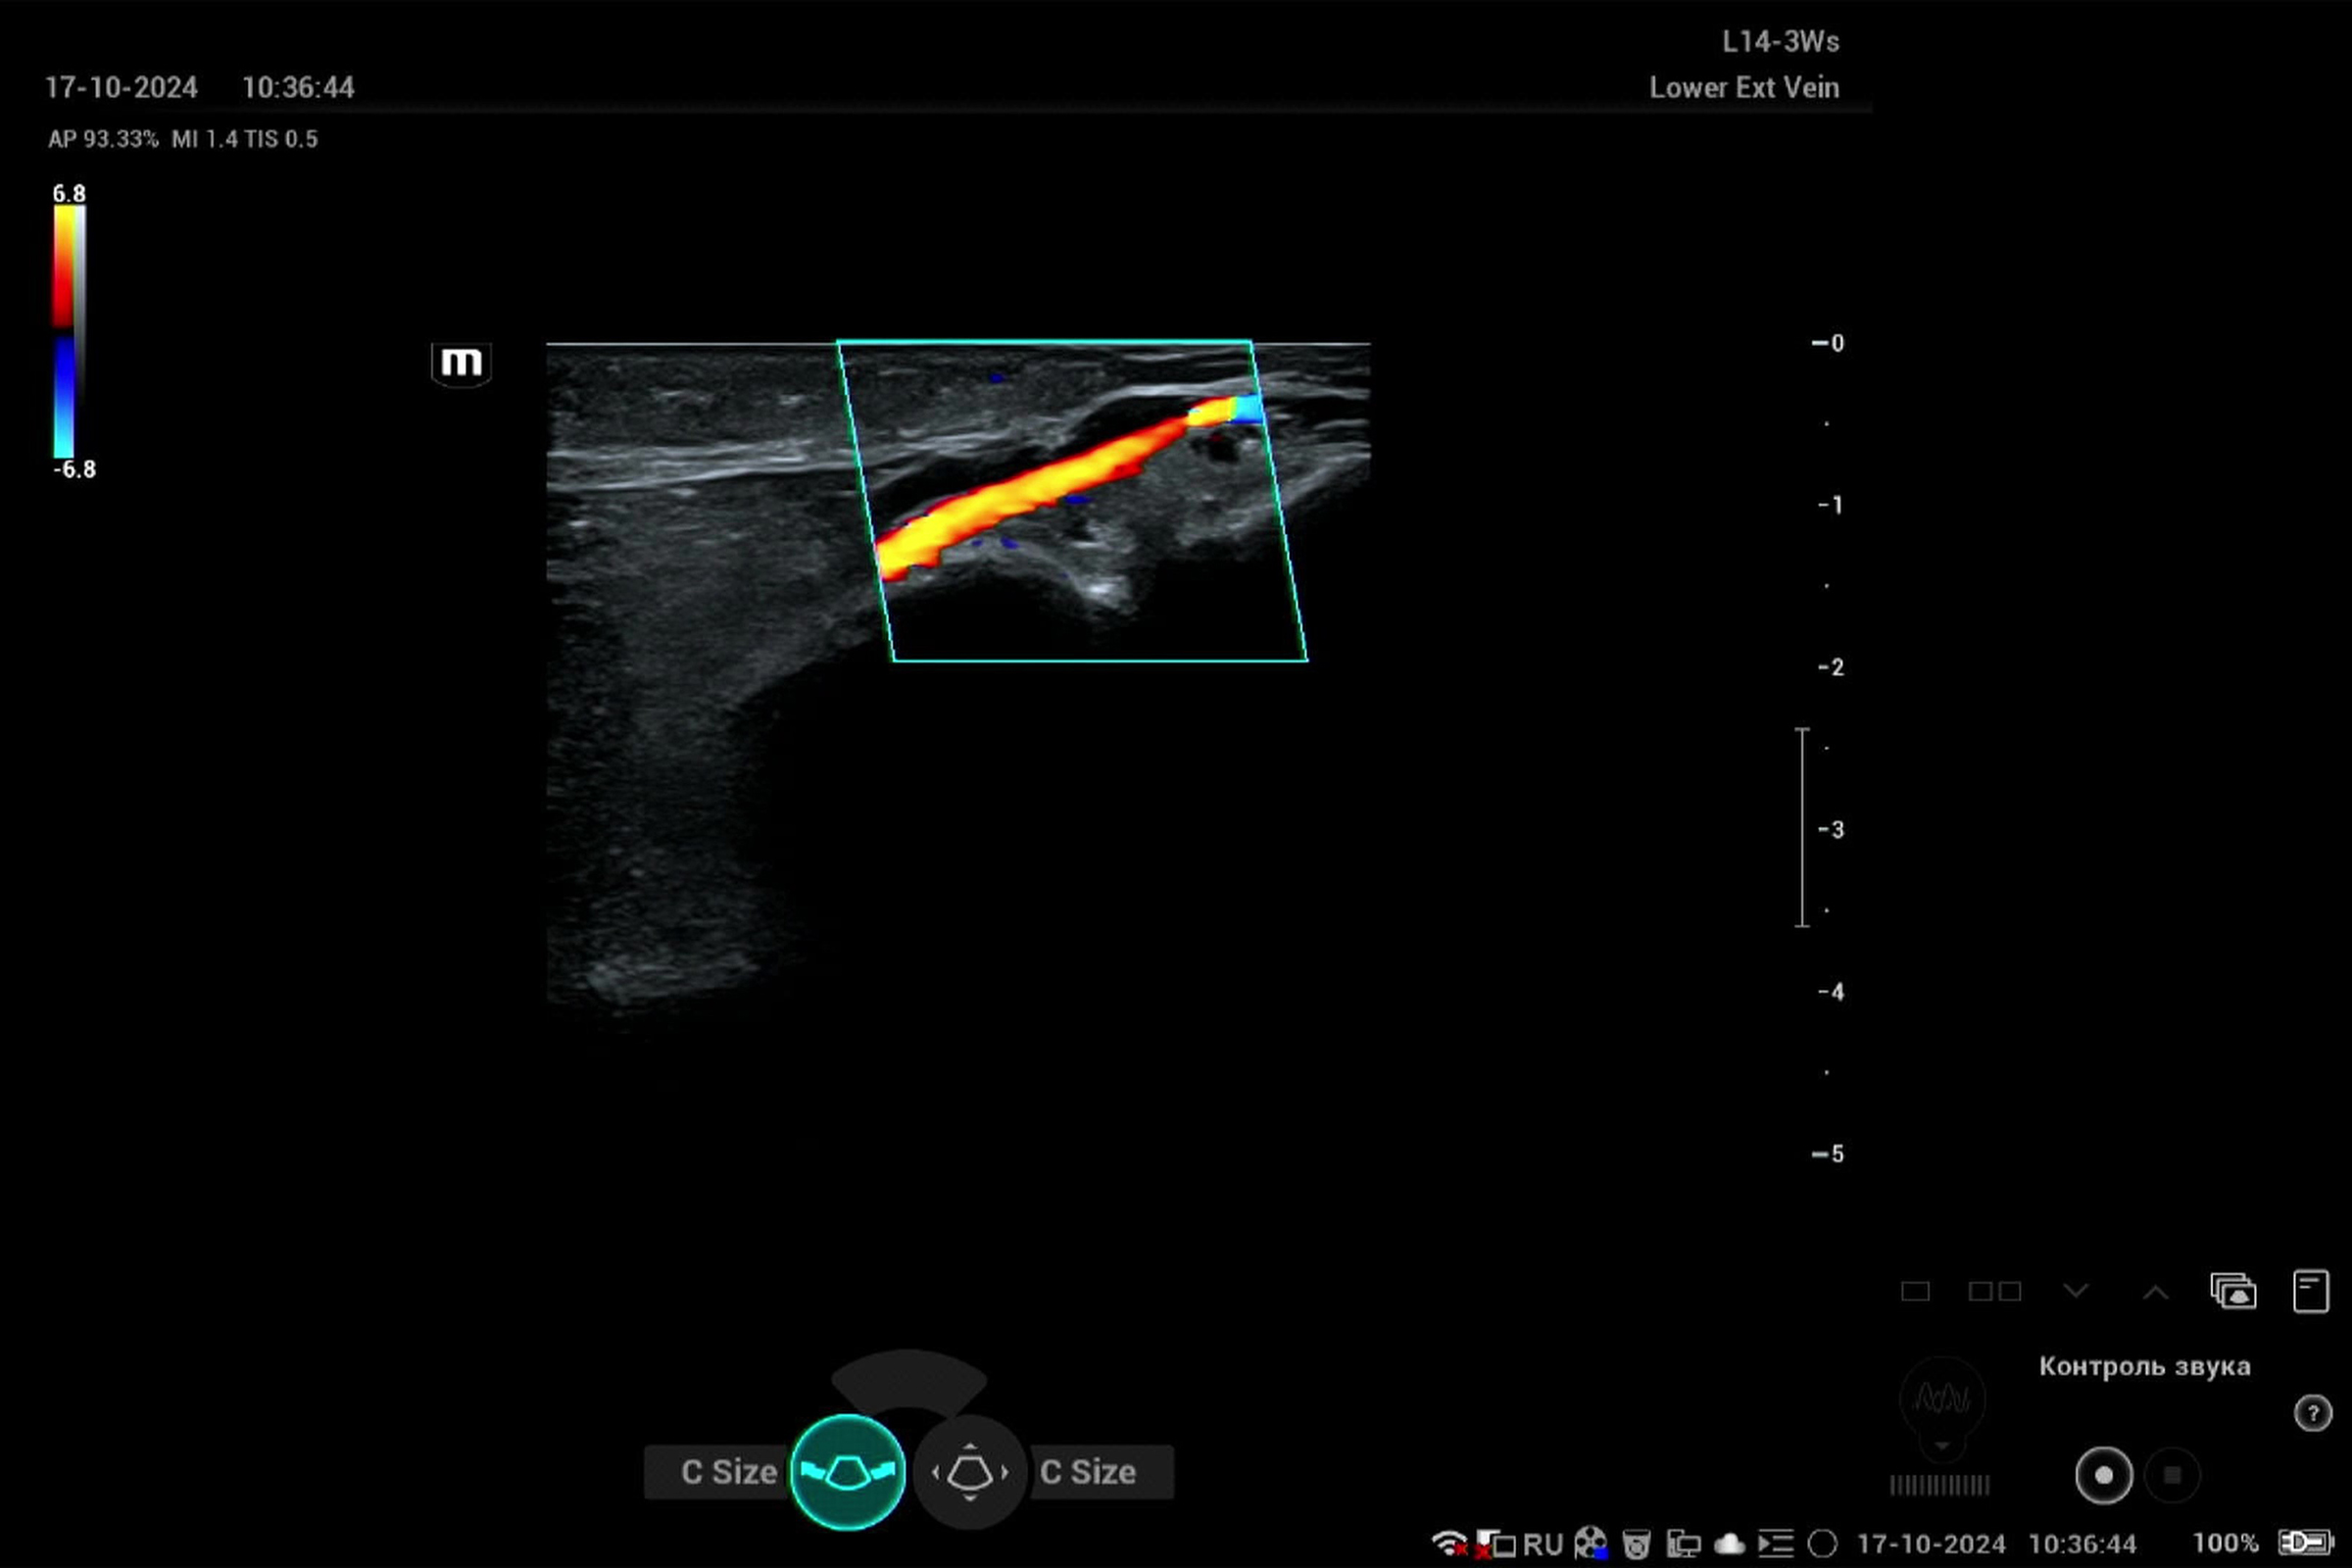

Узи вен химки